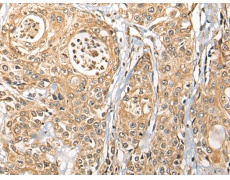

IHC positive control: |

Human prostate cancer |

IHC Recommend dilution: |

25-100 |